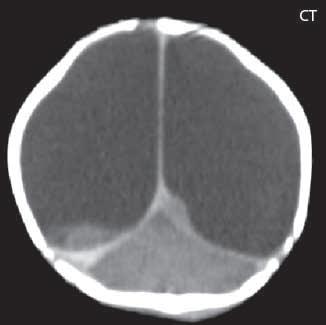

Dříve nazývaná také agyrie, značí chybění mozkových závitů a sulků (hladký mozek) nebo jejich redukci kromě vyznačené fossa Sylvi. Mozek je fyziologicky embryonálně „plochý“ do 26. týdne, pak začíná gyrifikace. Rozlišujeme lissencefalii typ I, příčina je obvykle na genetickém podkladě (delece 17p13 obsahující LIS1 gen, mutace pro doublecortin (DCX) na X chromozomu, mutace pro reelin gen na 7. chromozomu), ale snad může být způsobena i infekcí, exogenními látkami (abúzem alkoholu, iradiací…). Příčinou je zastavení neuronální migrace, mikroskopicky je kůra špatně strukturována, jsou pouze čtyři vrstvy nezralých neuronů na rozdíl od normálně organizované mozkové kůry, kde je šest vrstev. Makroskopicky pozorujeme velmi tenkou mozkovou kůru, dále vrstvu bílé hmoty mozkové a silnou vrstvu šedé hmoty mozkové, lemující kůru mozkovou, která obsahuje „mladé“, nezralé neurony, které byly „zastaveny“ během své cesty do mozkové kůry (jako by mozková kůra byla tvořena dvěma páskami šedé hmoty, mezi kterými je vrstva bílé hmoty mozkové). Povrch mozku je zcela plochý, nebo jeho gyry a sulky jsou výrazně redukovány. Mozek na koronálních řezech tvoří náznak čísla 8 (způsobené vertikální polohou fossa Sylvi).

Zobrazení

Pozorujeme, že povrch mozku je plochý, nebo jsou jeho gyry a sulky výrazně redukovány, ale mohou být současně i zobrazeny oblasti (více frontálně), kde mohou být patrné ploché gyry a mělké sulky. Pod mozkovou kůrou, která je nápadně tenká, lze diferencovat vrstvu bílé hmoty, která odděluje mozkovou kůru od silné, vnitřní vrstvy šedé

hmoty mozkové. Hypogeneze corpus callosum, hypoplazie mozkového kmene z redukce počtu kortikospinálních a kortikobulbárních vláken. Dle genetiky se někdy ještě dále lissencefalie rozdělují, např. LIS1 má nejvíce postiženu oblast parietookcipitální, u X-LIS (X-vázaná lissencefalie, DCX) převažuje postižení oblastí frontotemporální.

Obr. I.1.4a Lissencefalie typ I

Obr. I.1.4b Frontálně naznačená gyrifikace (šipka), kůra je nápadně tenká, vrstva bílé hmoty (přerušovaná šipka) odděluje mozkovou kůru od silné, vnitřní vrstvy šedé hmoty mozkové, lissencefalie typ I; stejný pacient jako na obr I 1 4a c d

Obr. I.1.4c Lissencefalie typ I